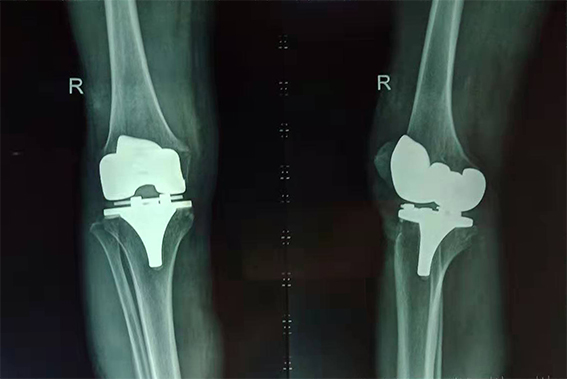

吳奶奶術(shù)后右膝X光片

經(jīng)過醫(yī)院專家組聯(lián)合會診,劉鴻程主任決定采用取右膝正中切口,依次切開皮膚、皮下組織、膝關(guān)節(jié)、顯露股骨遠(yuǎn)端及脛骨近端,松解內(nèi)外側(cè)軟組織,根據(jù)術(shù)中情況決定脛骨及股骨截骨平面,安裝假體;縫合關(guān)節(jié)囊腫、皮下組織及皮膚。手術(shù)過程中沒有任何肌肉或肌腱的切斷,對肌肉無損傷,術(shù)后發(fā)生假體脫位的風(fēng)險低,從而可以早期康復(fù)。